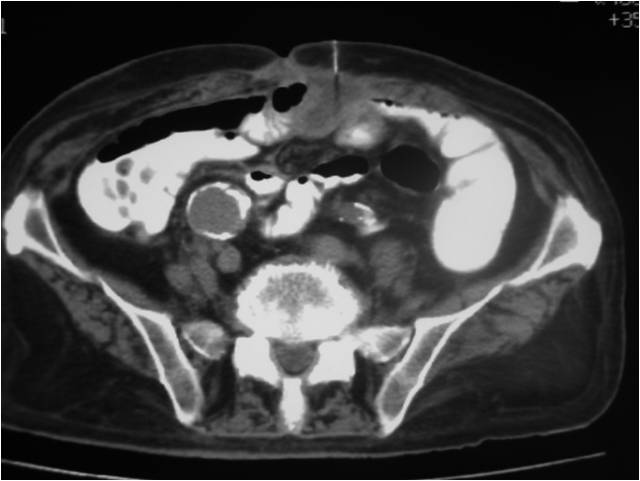

- Paracentisis of a deep pelvic abscess

- Successful catheter placement in a deep pelvic abscess